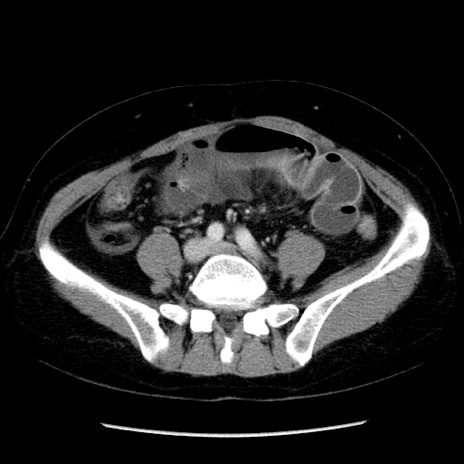

症例6(横断像)

【症例】50歳代女性

【主訴】下腹部痛

【現病歴】本日朝より下痢2回あり。 昼食を食べた後、嘔吐3回、下腹部痛認め、症状軽快せず、当院救急搬送。

最終食事:本日昼(生ものなし)。 昨日の夜、刺身を食ぺたとのこと。周囲に同様の症状の者なし。普段、排便は毎日あるとのこと。

【既往歴】卵巣癌術後(8年前に当院で卵巣摘出)

【身体所見】 意識清明、腹部:平坦、腸蠕動音→、やや硬、下腹部自発痛・圧痛あり、反跳痛あり、筋性防御なし。

【データ】WBC 16000、CRP 0.01